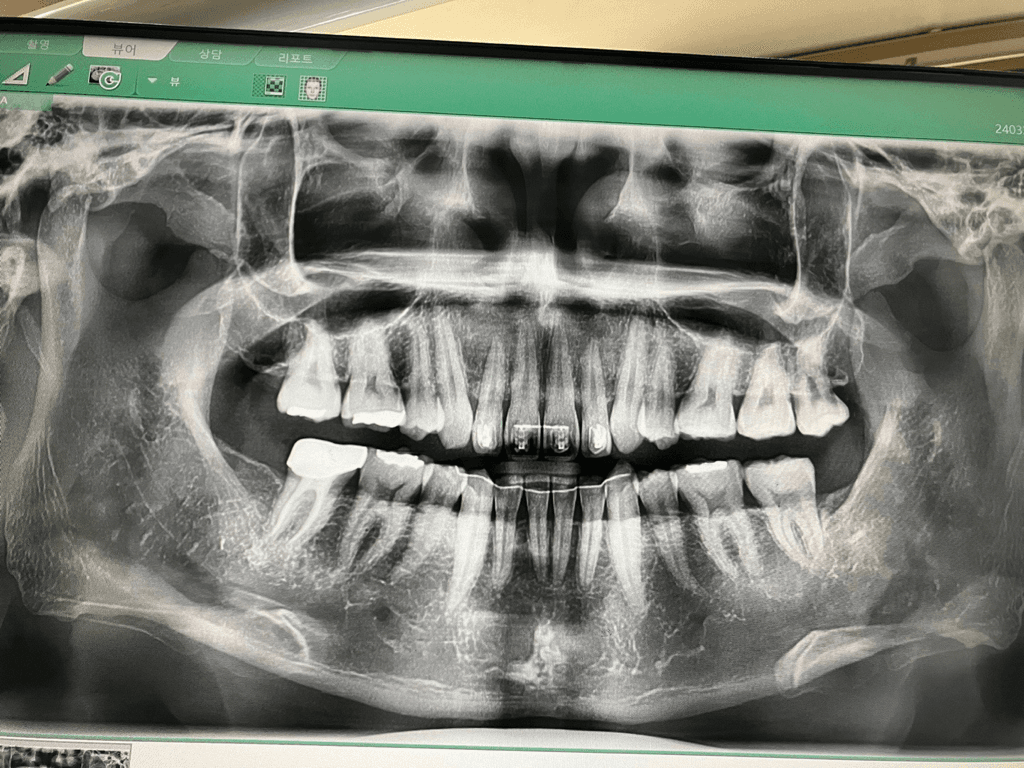

어떻게 하악이 뒤로 밀려있는지 알 수 있나요?

최근 치과에 방문 했는데 선생님이 하악이 뒤로 밀려있다고 말습하셨습니다.

위 사진에서 무엇을 보고 하악이 뒤로 밀려있는지 알 수가 있나요?

위 사진만 보고는 교합관계나 상악, 하악의 위치 관계를 정확히 파악하기는 어렵습니다. 현재 파노라마 방사선 사진상에서는 이전에 상,하악 발치교정을 시행했고 왼쪽 어금니 교합이 살짝 틀어져 있다는 것 정도만 알 수 있습니다.

파노라마 방사선 사진을 통해서는 교합 양상을 제대로 알 수 없으며, 아마 주치의선생님께서 육안으로 보시기에 그러한 판단을 내리신 것으로 보입니다.

파노라마 사진에서는 관찰할 수 없고 직접 눈으로 봐서 교합상태를 확인해야 알 수 있습니다.

파노라마 사진으로는 하악과 상악의 관계를 알수가 없습니다. 육안상으로 그렇다는게 아닐까 생각됩니다.

파노라마 사진으로는 화학이 뒤로 후퇴했는지 알 수 있는 방법이 없습니다. 화학이 뒤로 후퇴했는지를 확인해보기 위해서 일단은 세펄로라는 사진을 찍어보는 것이 좋습니다